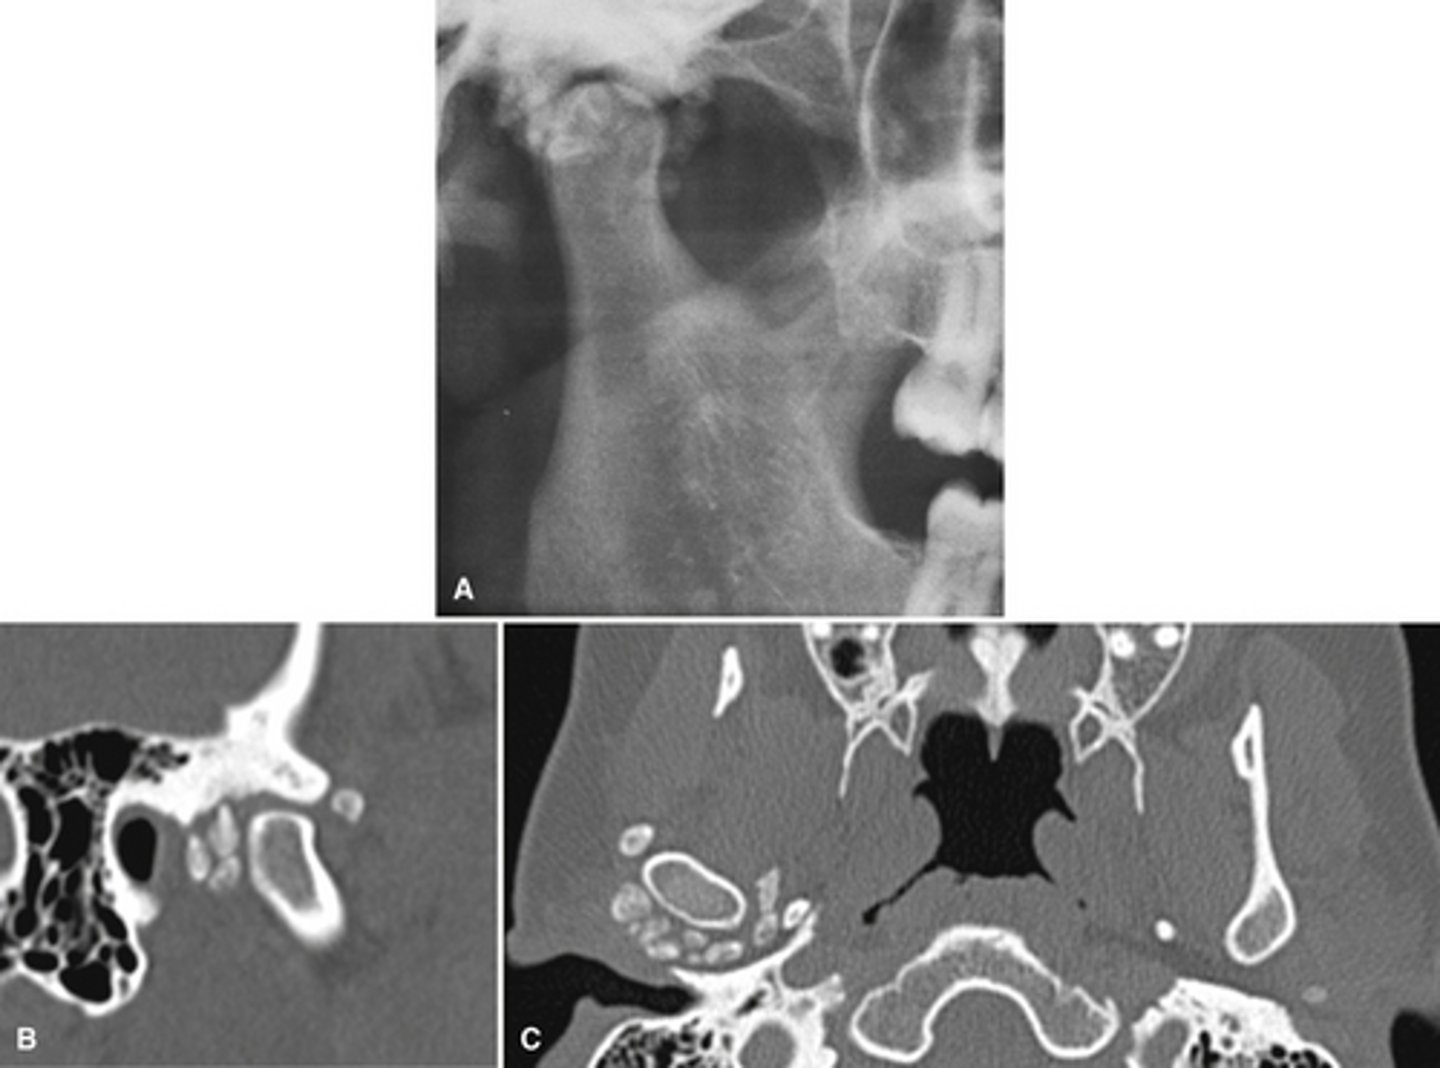

Patient has DJD.

The top images show the subchondral/ Ely cyst, a pseudocyst of connective tissue, granular tissue and osteoid, the bottom images show the same patients left side with broad erosion, a lack of cortication, loss of joint space.

What is the diagnosis of the patient based off these radiographs and what are the features? (Top images = patients right condyle) (bottom images= same patients left condyle)